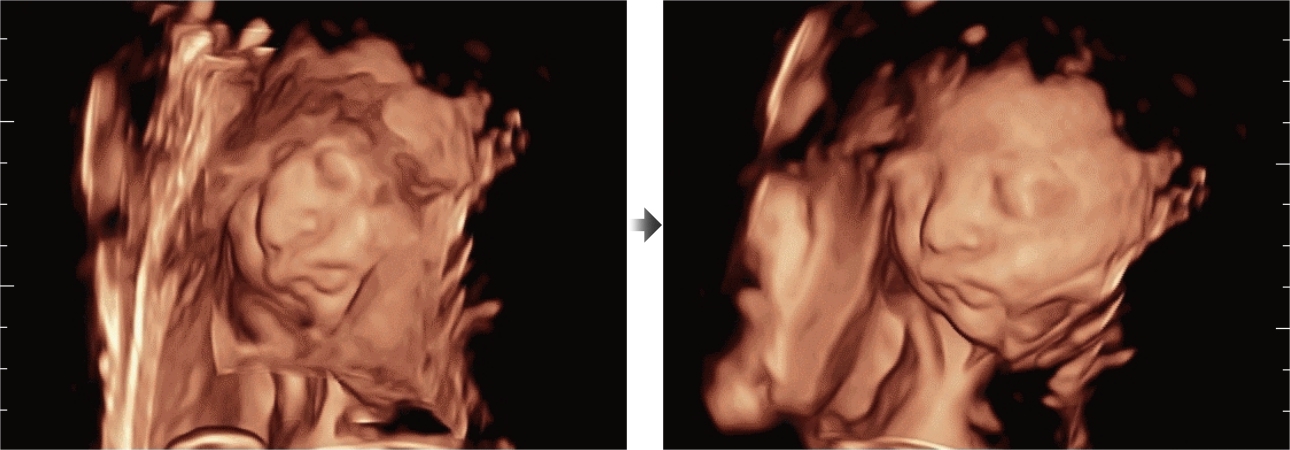

As well as the premium level image quality, Resona 7 also enhances clinical research capabilities with the revolutionary V Flow for vascular hemodynamic evaluation, and the most intelligent plane acquisition from 3D datasets for fetal CNS diagnosis. Combining the most intuitive gesture-based multi-touch operation and all the essential clinical features, Resona 7 is truly leading new waves in ultrasound innovation.